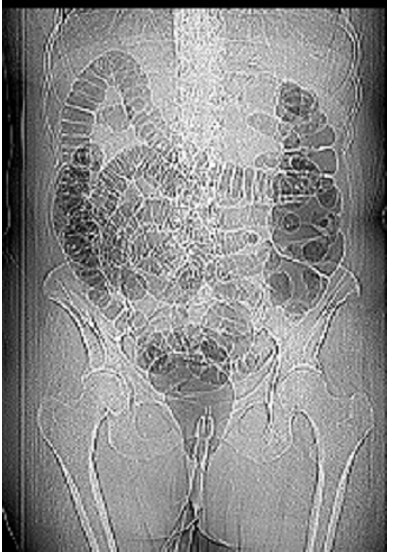

![]() |

| One patient was unable to retain the CO2 gas during insufflation. The problem was solved with the addition of a large rectal catheter and a retention balloon, and by taping the buttocks together. Image courtesy of Dr. Arnold Friedman. |